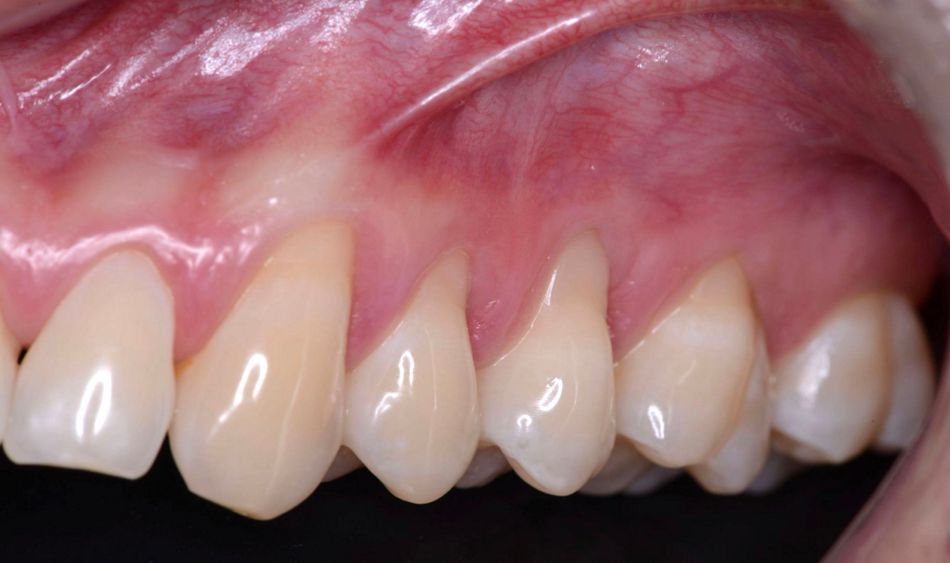

Initial situation

A 24-year-old male patient without any medical history or smoking habits, well-controlled oral hygiene, presented generalized gingival recessions in upper jaw. The patient reported tooth brushing with high forces and no gentle tooth brush. Clinical examination evidenced Miller Class I recession without hypersensitivity.